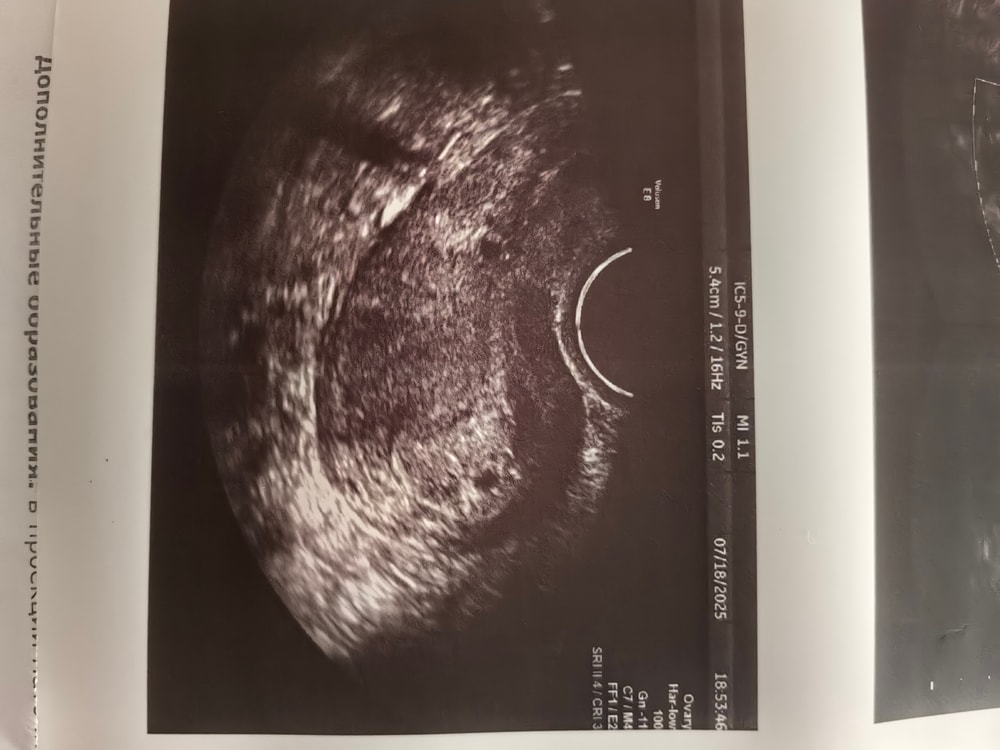

Изображение